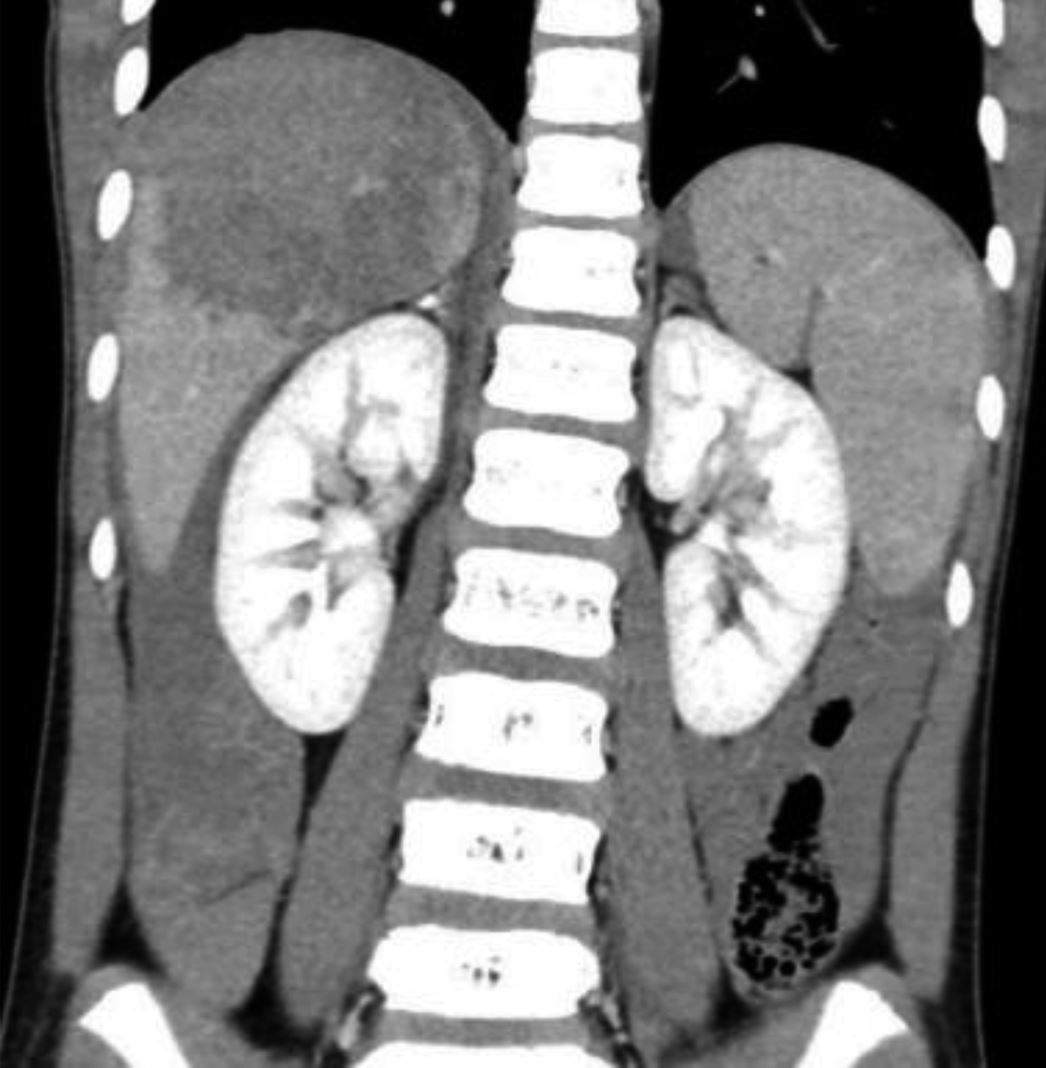

Ein neunjähriger Junge wurde nach einem Schlittenunfall notfallmäßig in der Kinderklinik vorgestellt. Sein Vater trug ihn auf dem Arm in die Notaufnahme, da der Rettungsdienst nicht verständigt worden war. Der Junge war zusammen mit einem Freund, beide ohne Helm oder Schutzkleidung, eine steile Abfahrt hinuntergefahren. Während der Junge auf dem Schlitten lag, saß sein Freund auf ihm. Die beiden prallten mit hoher Geschwindigkeit gegen einen Mast. Seitdem hatte der Junge zunehmende Bauchschmerzen. Sein Hautkolorit war blass, er atmete angestrengt und hatte einen angespannten Bauch. Seine Gelenke waren frei beweglich, aber er wirkte schmerzgeplagt und war kaltschweißig. Der Junge war allseits orientiert. Die Herzfrequenz betrug 160 Schläge pro Minute, der Blutdruck lag bei 83/65 mmHg, und die pulsoxymetrisch gemessene Sauerstoffsättigung betrug 100 %. Äußerlich waren eine Platzwunde an der Stirn (Abb. 1) und eine kleine thorakale Prellmarke sichtbar. Umgehend erfolgten eine Sonografie und danach eine Computertomografie des Abdomens (Abb. 2 und 3).

Abb. 3

: Computertomografie des Abdomens

© GKM